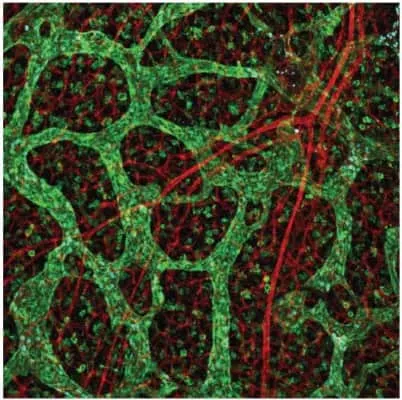

| Angiogenesis | |

| Lymphatics | |